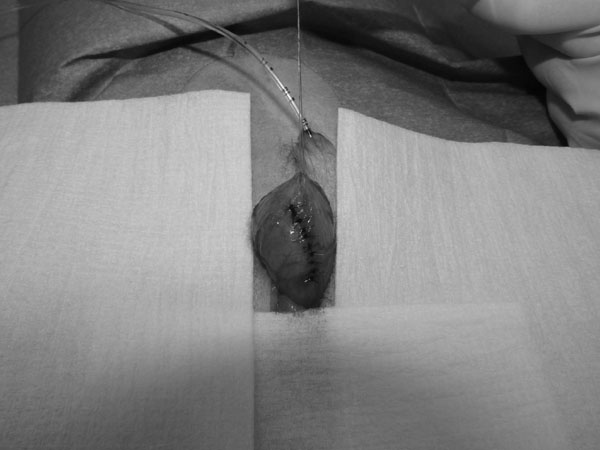

5~6歳以上の去勢手術をしていないオス犬に多い病気ですが、メス犬や去勢した犬に起こることもあります。お尻の筋肉が萎縮した結果、筋肉の隙間から直腸や膀胱が皮膚の下にとびでてしまいます。これにより便が出にくくなったり膀胱炎になったりします。手術をすることで機能回復および今後の致死的な状況を回避することができます。当院では去勢手術→結腸固定→前立腺固定→骨盤隔膜構成筋の縫縮→内閉鎖筋フラップ→浅臀筋フラップの順で通常腹側・臀部左右両側同時に行います。また老化以外に、筋肉が萎縮する原因があったり、腹圧がかかる原因があったりする場合も多いので、再発防止のためそれらの診断・治療も重要です。今回のワンちゃんも無事手術も終わり元気に退院しました。よかったね。